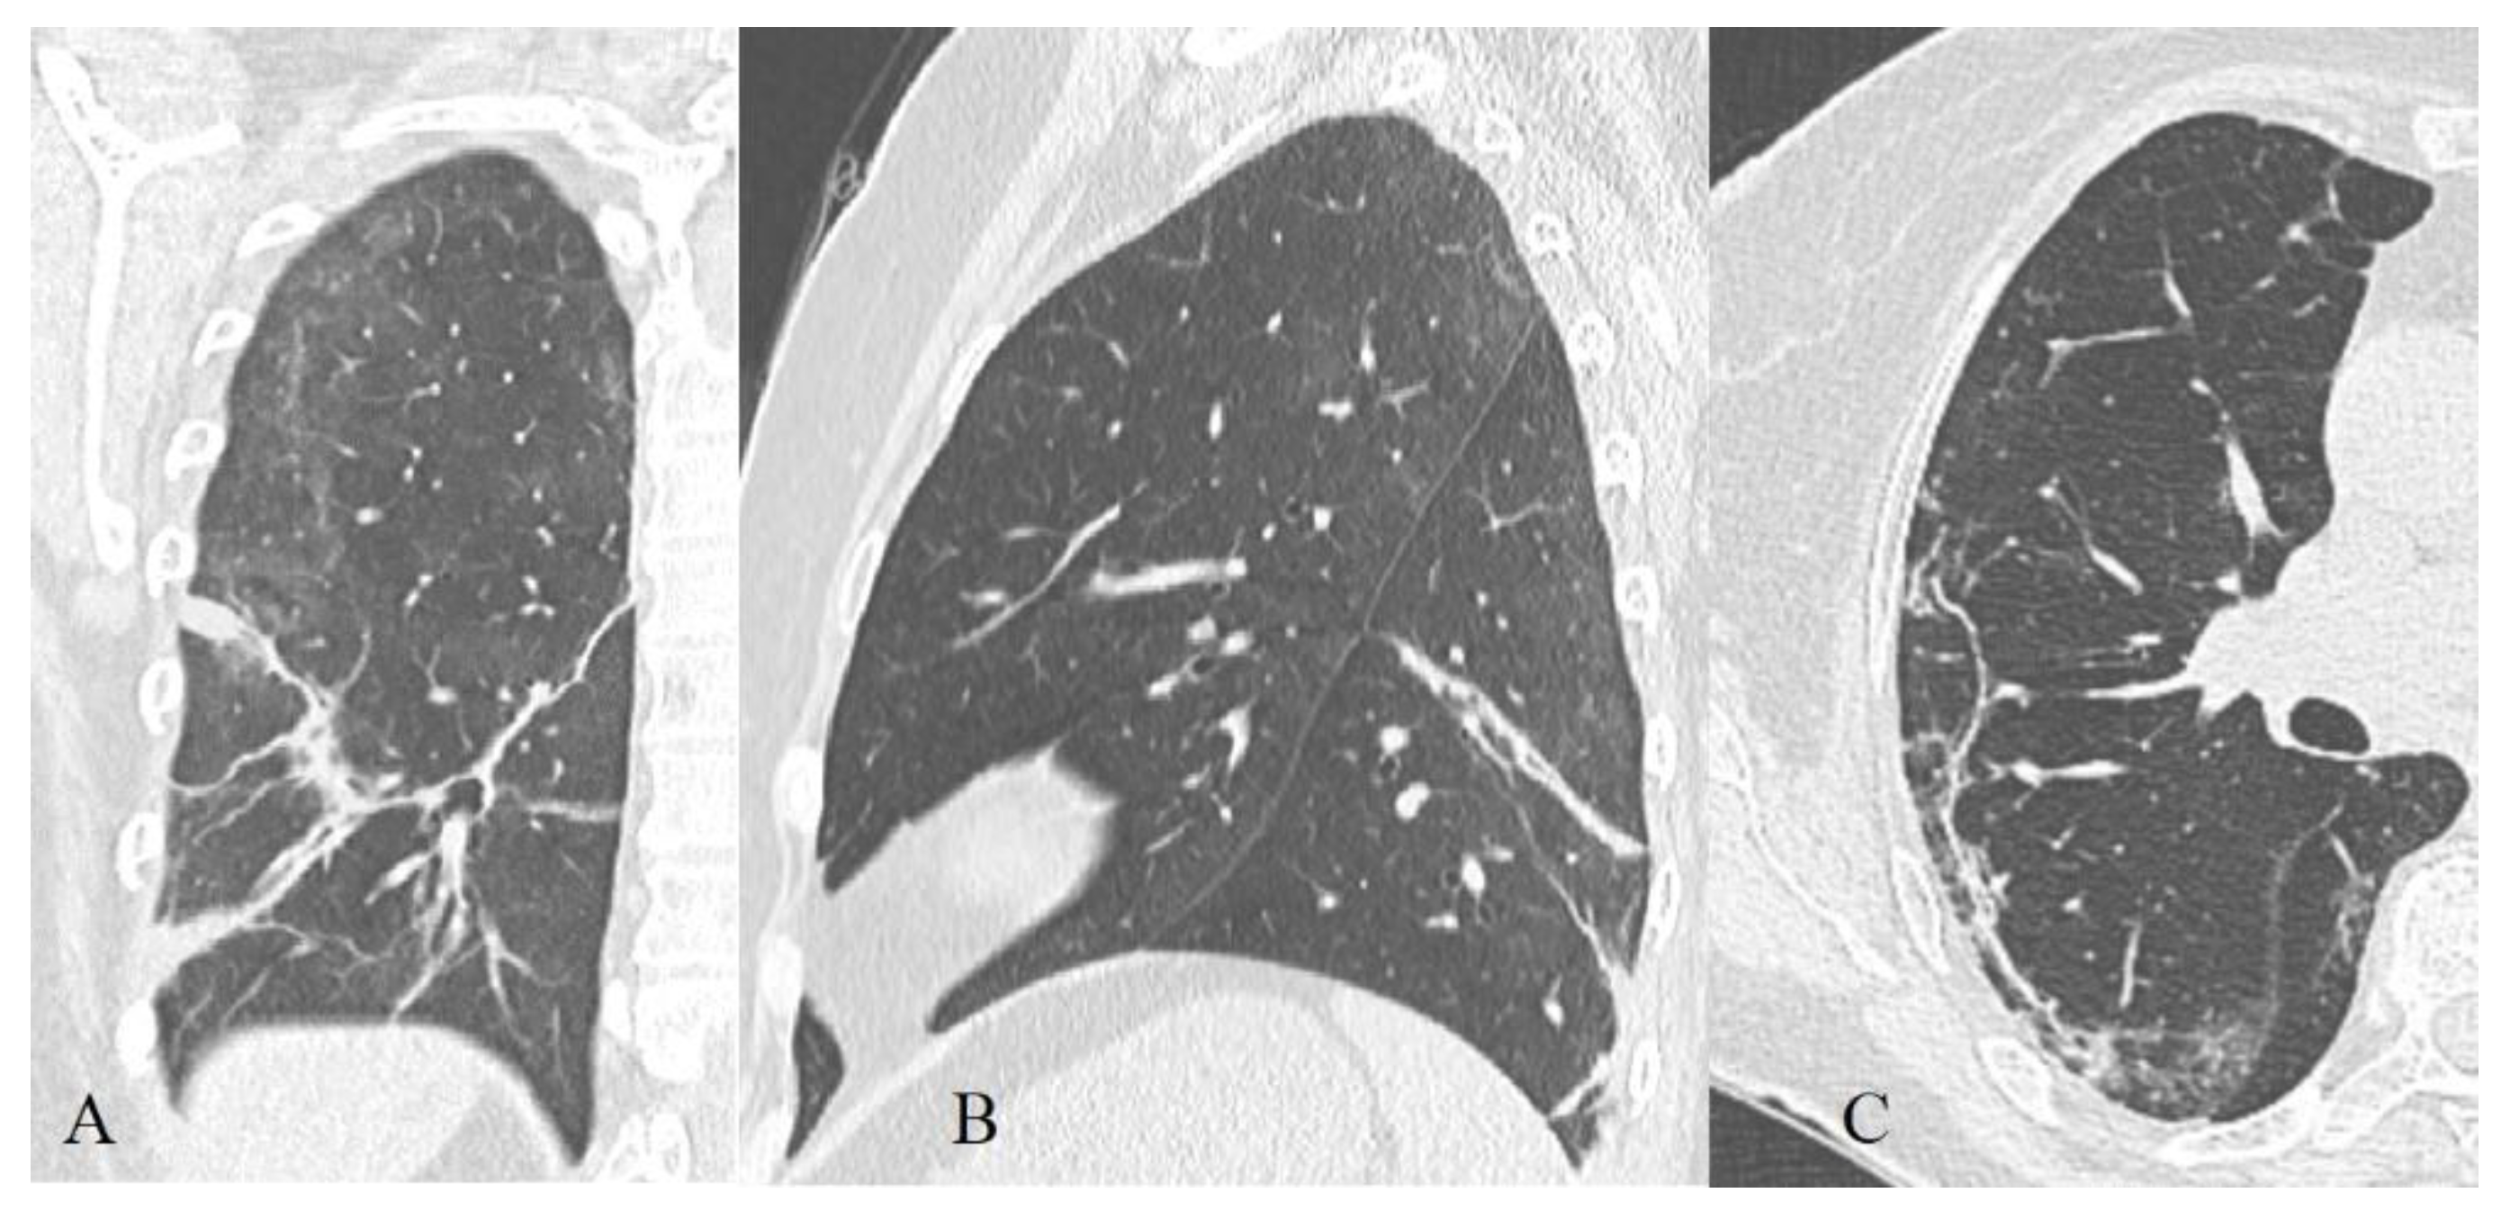

3.2.5. Localization, Shape, and Volume of the Lesion

- Resolution (>14 days): an increase in the volume of the air pulmonary parenchyma with the appearance and predominant contribution of RC, parenchymal bands, and subpleural lines, a reversible halo (signs of organizing pneumonia). At the same time, there is a decrease in the contribution of the combination of GGO and consolidations to the overall CT picture (~9%), with the beginning of a downward trend in the contribution of the combination of GGO and RC (~66%). The contribution of the isolated GGO pattern remained unchanged in comparison with the previous phase (~22%) [43] since consolidation was probably resolved into GGO.

- Resolution (>14 days): predominant contribution of consolidations and RC in both cohorts, at the same time there is a decrease in the contribution of GGO, but CP contribution decreased more slowly in deceased than in recovered patients.